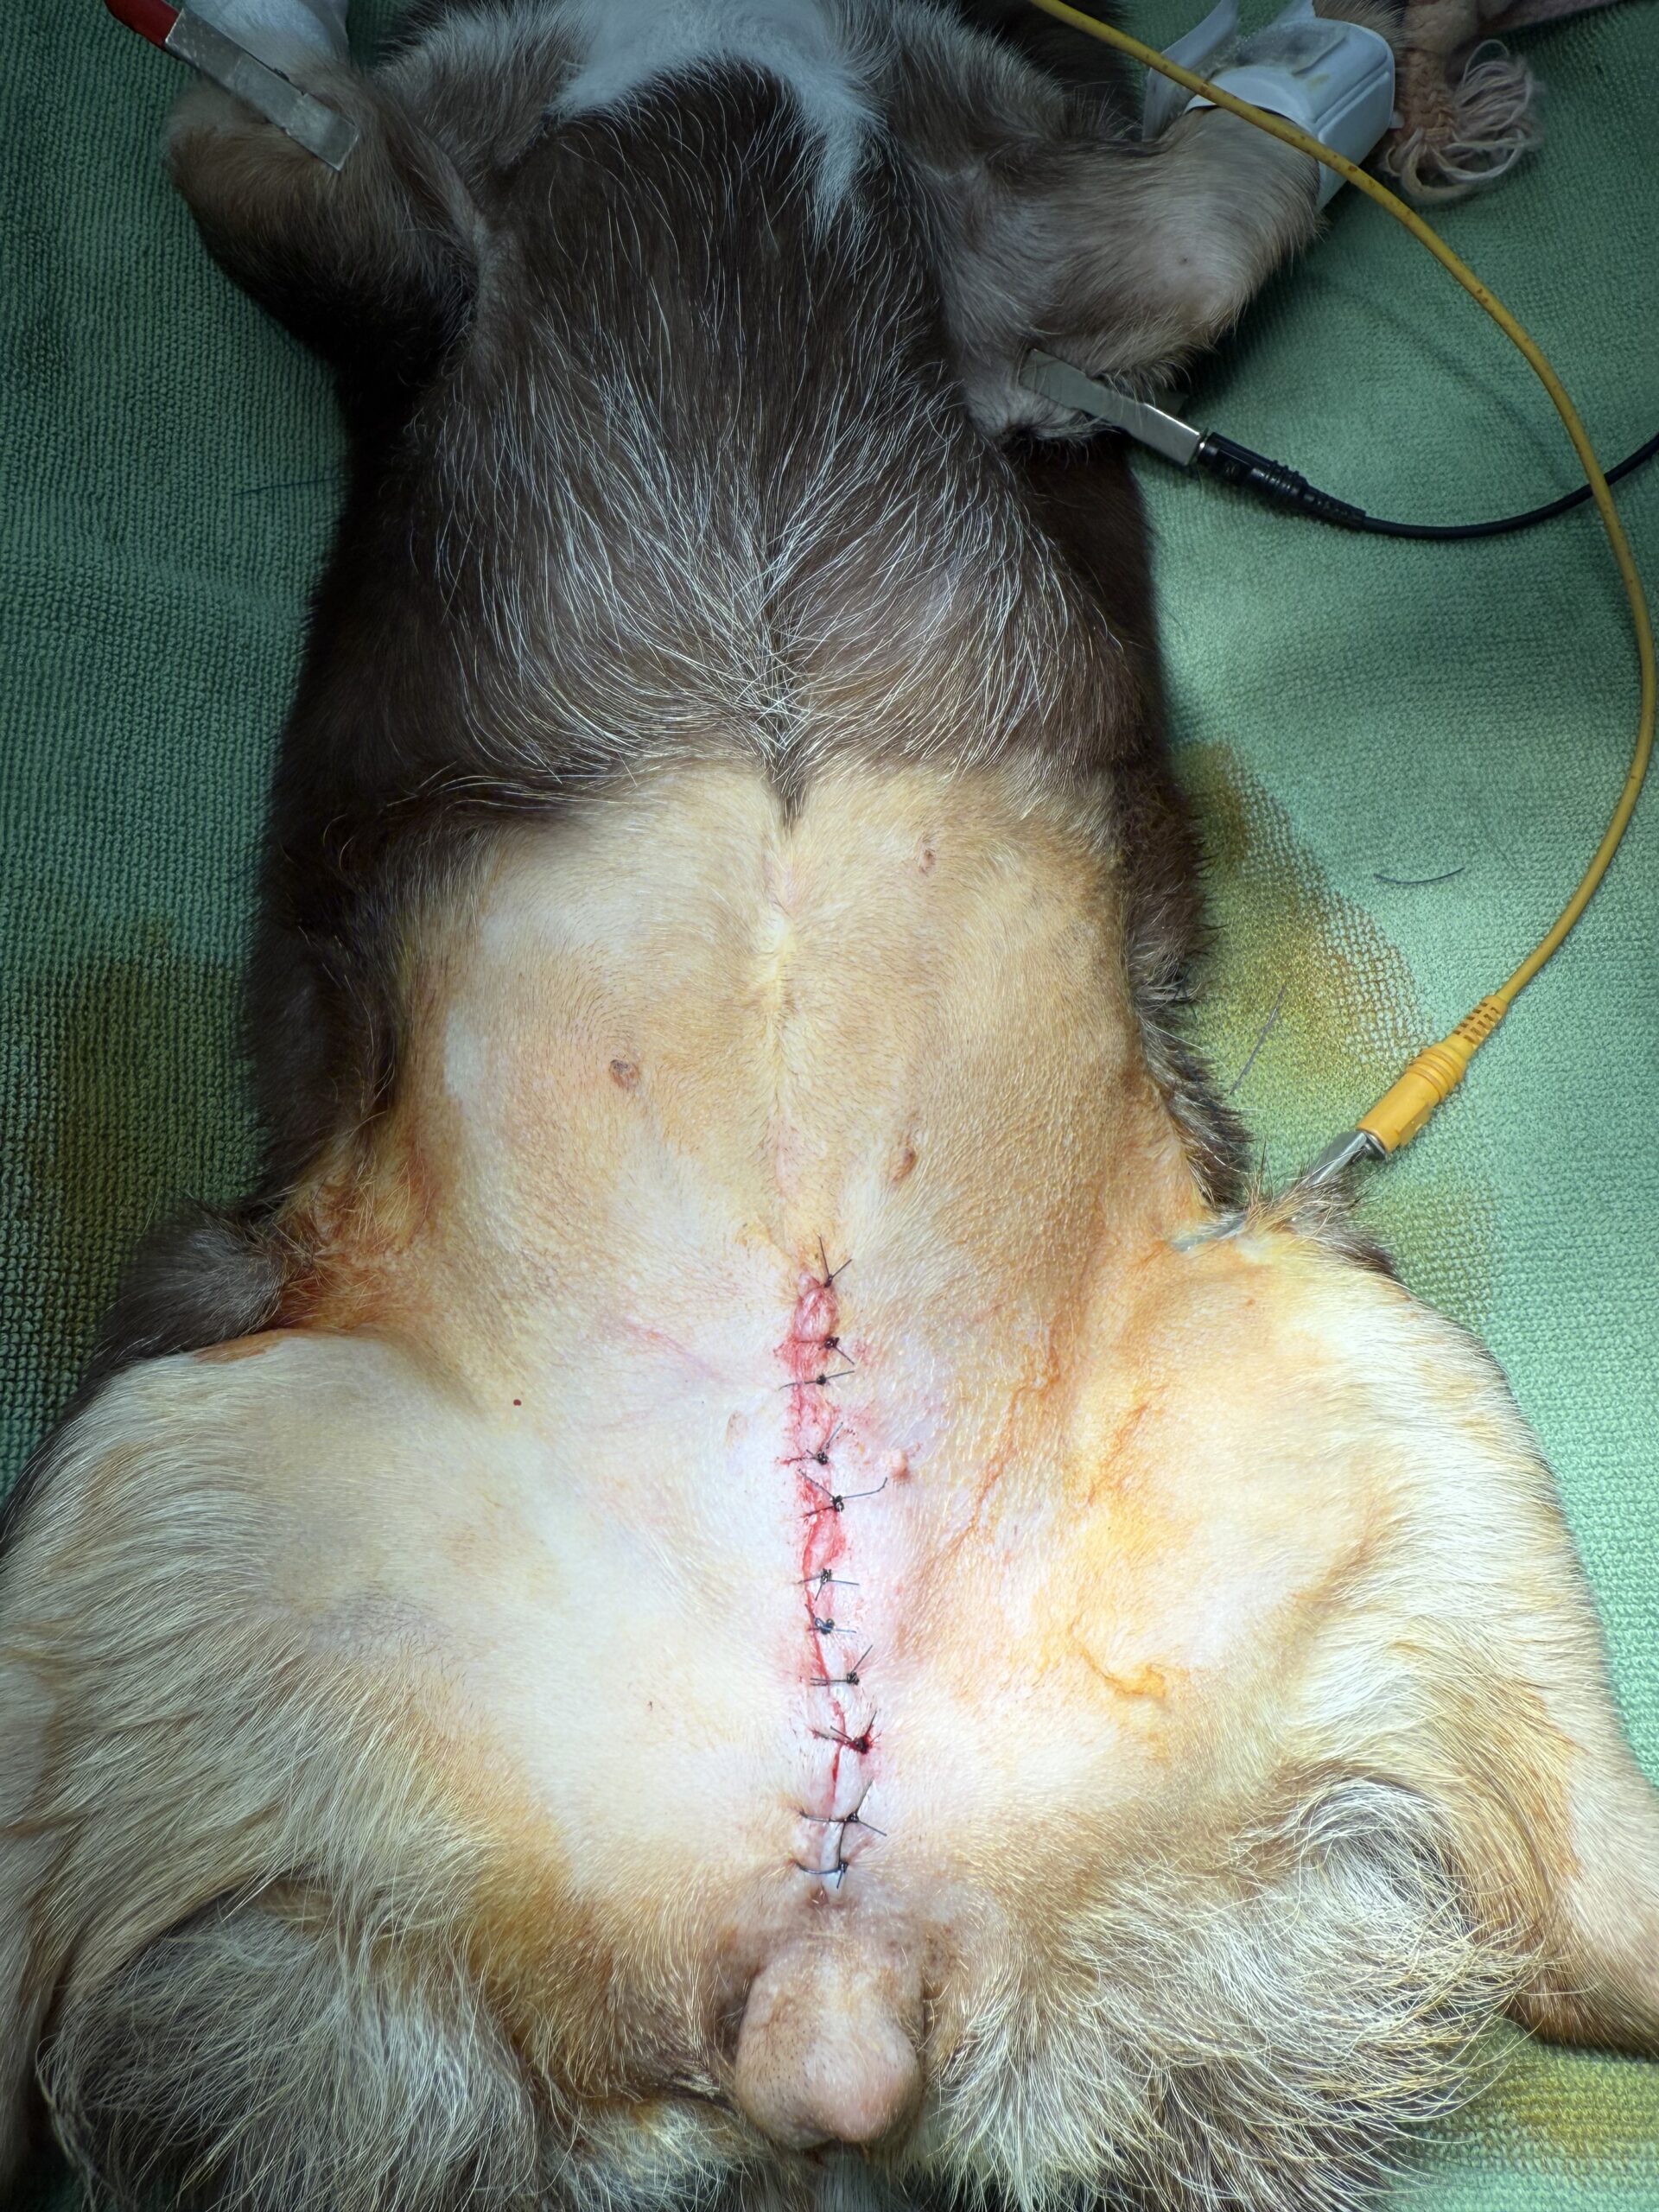

動物種:チワワ

年齢:12歳

性別:避妊済みのメス

症状:下腹部の腫れ。小さくなったり大きくなったりする。

診断:鼠径ヘルニア

治療方針:鼠径輪の閉鎖

経過・予後:術後1ヶ月以上の経過観察で、再脱出などの問題は認められていません。

写真